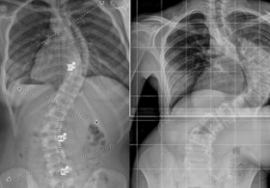

تابعت الدراسة مجموعة من الفتيات قبل البلوغ وأثناء بدايته، وجميعهن يعانين من جنف بسيط إلى متوسط ويستخدمن الحزام الطبي كعلاج.

تمت مراقبة عدة أمور خلال الزيارات الدورية، منها:

قياس درجة الانحناء.

قياس الطول الكلي للجسم.

قياس طول العمود الفقري.

متابعة التغيرات خلال فترة النمو السريع.

ثم تم تحليل العلاقة بين سرعة نمو العمود الفقري وسرعة زيادة درجة الانحناء.